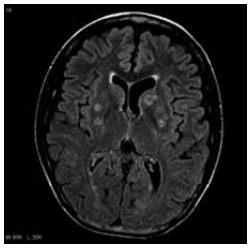

Paciente do sexo masculino, de 49 anos, portador de HIV

diagnosticado há dez anos, interrompeu a TARV há três

anos. Procura o pronto-socorro com cefaleia progressiva

há quatro semanas, associada a febre, sendo internado

na unidade de terapia intensiva por confusão mental e

fraqueza em hemicorpo esquerdo. Ao exame físico:

desorientado, paresia grau 3/5 em membro superior

esquerdo, sem rigidez de nuca. Realizou a ressonância

de crânio mostrada a seguir:

Qual é o diagnóstico clínico associado?